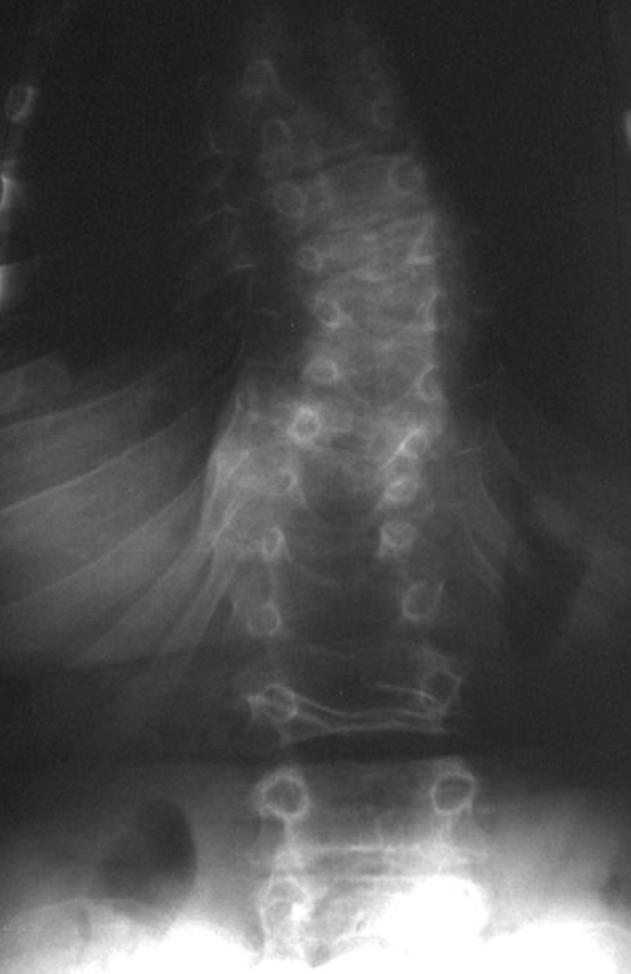

Kniest Dysplasia: New Radiographic Features in the Skeleton.

To describe skeletal findings in patients with Kniest dysplasia, focusing on osseous abnormalities that have not been characteristically associated with this disorder.

Bilateral radial head dislocations and bilateral clubfeet were seen in our series. Other characteristic findings for this dysplasia were seen in all four patients.

Clubfeet and radial head dislocations may be associated with Kniest dysplasia. The presence of these osseous findings in the context of multiple skeletal abnormalities suggestive of a skeletal dysplasia should indicate the possibility of Kniest dysplasia and pathognomonic features for this entity should be sought.